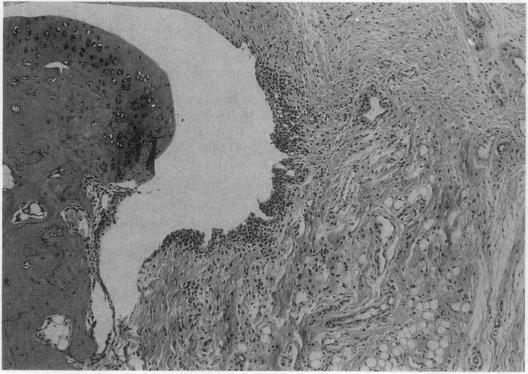

Many different agents, including mineral oil and silicone, have the capacity to act as immunological adjuvants, i.e., they can contribute to the activation of the immune system. Some adjuvants, including mineral oil, are known to induce arthritis in certain strains of rats after intradermal injection or percutaneous application. The aim of this study was to determine if common commercial cosmetic products containing mineral oil could induce arthritis in the highly susceptible DA (Dark Agouti) rat. Intradermal injection of five out of eight assayed cosmetic products without further additives resulted in arthritis with synovitis. One of the products induced a very aggressive arthritis, which had declined after 5-9 weeks. When this product was also assayed for arthritogenicity upon percutaneous administration, it induced a mild and transient arthritis in 5 out of 10 DA rats, whereas control animals showed no clinical signs of joint involvement. No arthritic reaction was seen in rats after peroral feeding with the most arthritogenic product or by intravaginal application of Freund's adjuvants. Silicone gel implants in DA rats did not cause arthritis. We conclude that mineral oils included in common commercially available products retain their adjuvant properties and are arthritogenic in the presently investigated arthritis-prone rat strain. There is yet no evidence that mineral oils present in cosmetics may contribute to arthritis in humans, but we suggest that this question should be subject to further investigation.